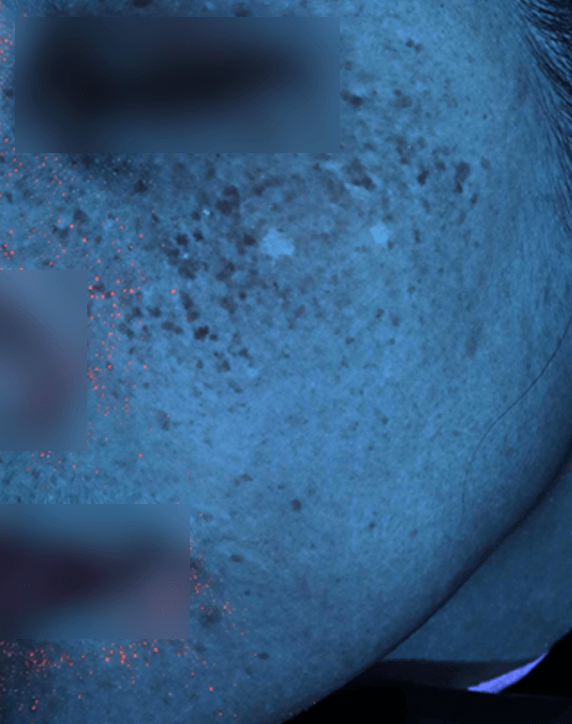

자외선광 1회차 / 10회차

2025.02.24